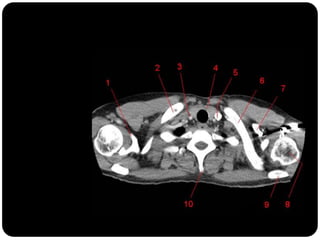

Brônquios segmentares

Esquerdo



Pulmão direito

Superior: direito

inferior: esquerdo

Vias aéreas

Traquéia

Brônquios

Bronquíolos

Alvéolos

 Pulmão direito:

 LSD: anterior, apical e posterior;

 LM: medial e lateral;

 LID: superior, basal medial, basal lateral,

basal anterior, basal posterior;

 Pulmão esquerdo:

 LSE: apicoposterior, anterior,

superior(língula), inferior(língula);

 LIE: segmento superior, basal antero-

medial, basal lateral e basal posterior;